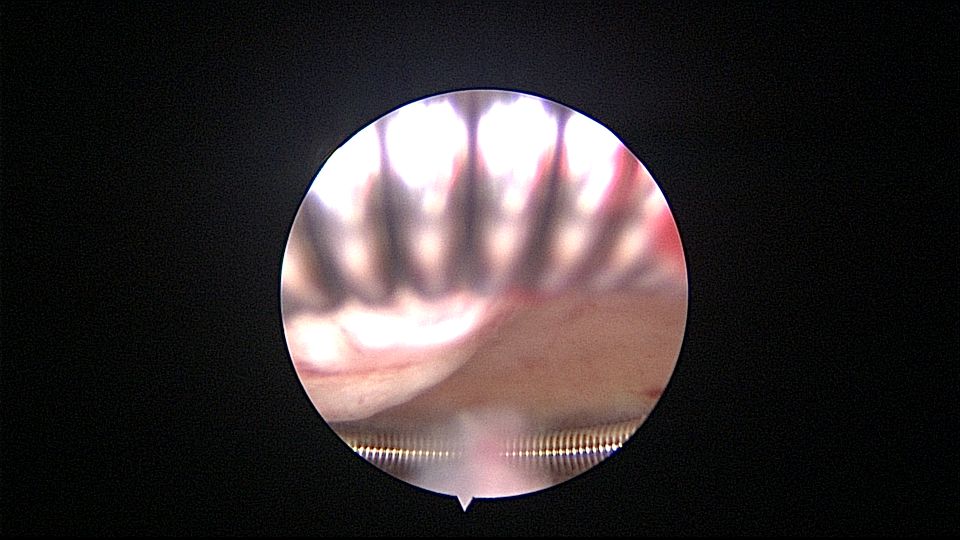

患者55岁,G1P1,顺产1次。安环34年,闭经半年,2天前外院取环失败,感下腹疼痛不适。术前复查B超,子宫前壁肌瘤直径4cm,宫内节育器回声。术中见子宫前倾后屈位,宫颈外口见息肉,镜鞘旋转扩宫进入宫腔,O型环位置正常,宫腔右前壁见直径2.5cm肌瘤结节突向宫腔,取环钩顺利取出节育环,宫腔无其他异常。该患者常规取环时未膨宫,子宫位置特殊,加之子宫受刺激后肌瘤凸向宫腔,可能对取环器械形成支点及杠杆效应,取环器械难以到达节育环位置,导致取环失败。